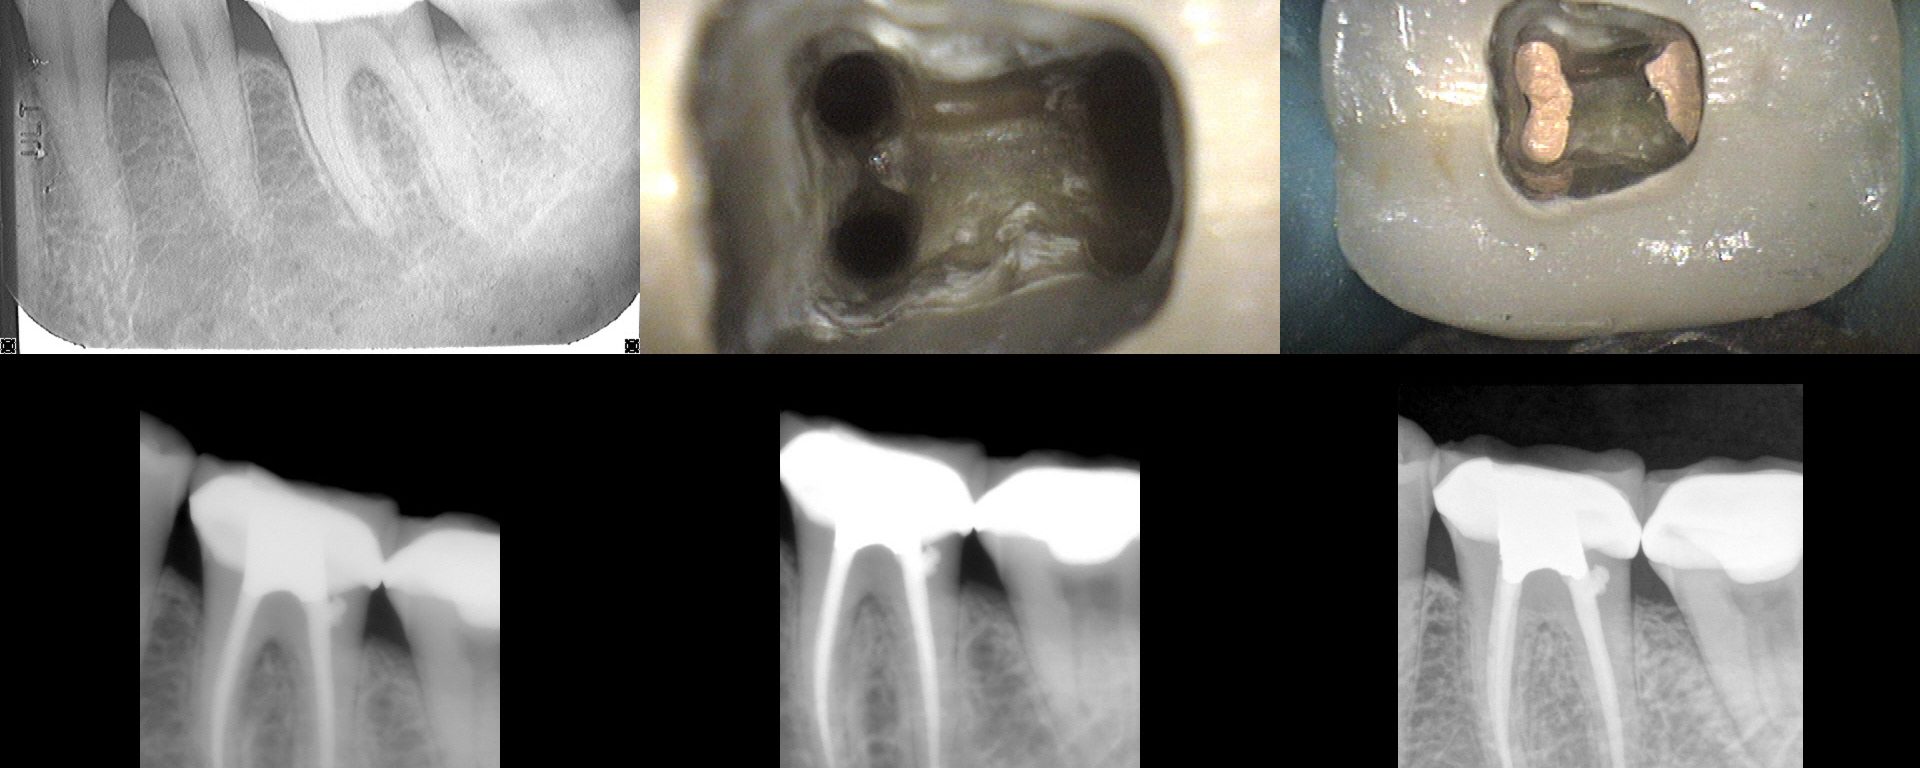

Here, traditional access would have removed most of the remaining PCD.  We leveraged the caries and existing loss of tooth structure at the mesial, and poked a hole in the distal with an EG4.  Chairside in the scope manages the field and NaOCl irrigation easily. Temporary was left off with hygiene instructions.  Tissue was healing […]

Nec/SAP. I had a historical on this from 2005…subsequent to which a Zirc was placed. I took a look at it and knew there wasn't going to be any point in a traditional access…i.e. even if I cut a traditional access, it would be a search and try-not-to-destroy in the roots.  Found four PONs. CBCT […]